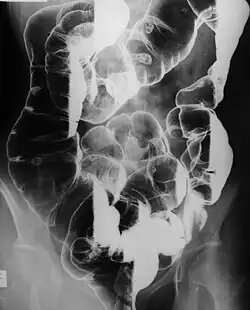

Un clisma opaco è una procedura medica utilizzata per esaminare e diagnosticare varie problematiche del colon umano (intestino crasso). Immagini a raggi X vengono effettuate mentre un mezzo di contrasto, generalmente solfato di bario, riempie il colon attraverso il retto.

Nei pazienti sani, il bario riempie il colon in modo uniforme e mostra un contorno normale dell'intestino, la sua pervietà (dovrebbe essere liberamente aperto), e la sua posizione.